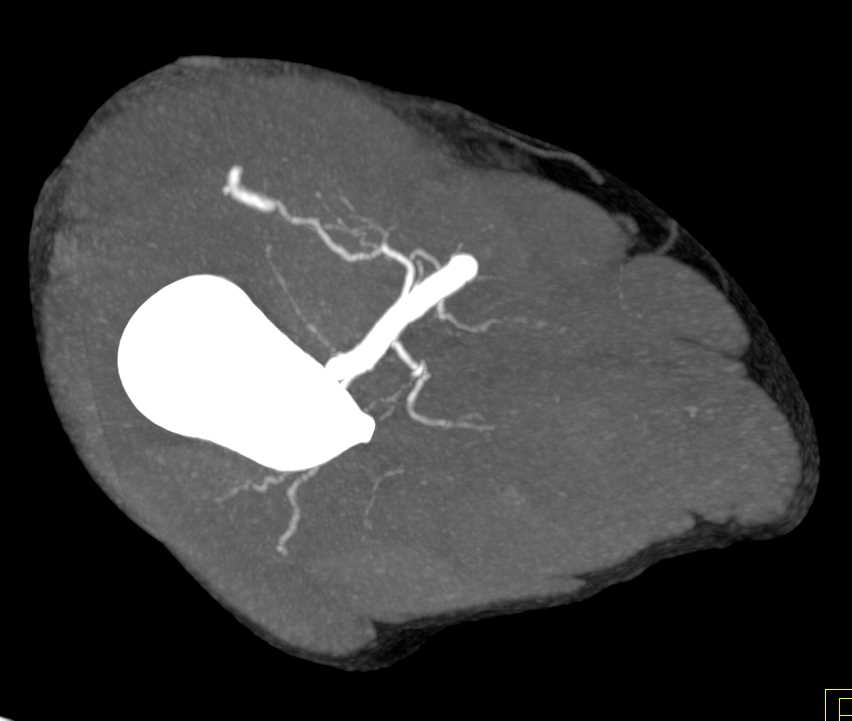

GSW with Bleed Near Knee